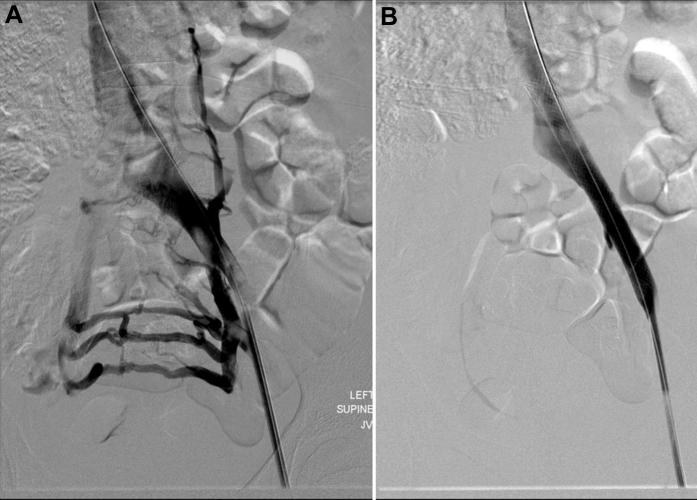

静脉闭塞治疗患者的近红外荧光淋巴成像

Near-infrared fluorescence lymphatic imaging in a patient treated for venous occlusion.

Although lower extremity edema/lymphedema can result from venous and/or lymphatic abnormalities, effective treatment depends upon understanding their relative contributions to the condition. Herein we use near-infrared fluorescence lymphatic imaging in a 16 year-old female diagnosed with unilateral lymphedema of the right leg and previously treated with left iliac vein stenting in an attempt to alleviate lymphedema. The imaging shows that abnormal lymphatic anatomy, rather than venous occlusion, was likely responsible for unilateral swelling.

虽然下肢水肿/淋巴水肿可能由静脉和/或淋巴异常引起,但有效的治疗取决于了解它们对病情的相对影响。在此,我们对一名16岁女性进行了近红外荧光淋巴成像检查,该女性被诊断为右腿单侧淋巴水肿,此前曾接受左髂静脉支架置入术以缓解淋巴水肿。成像显示,异常的淋巴解剖结构而非静脉阻塞可能是单侧肿胀的原因。